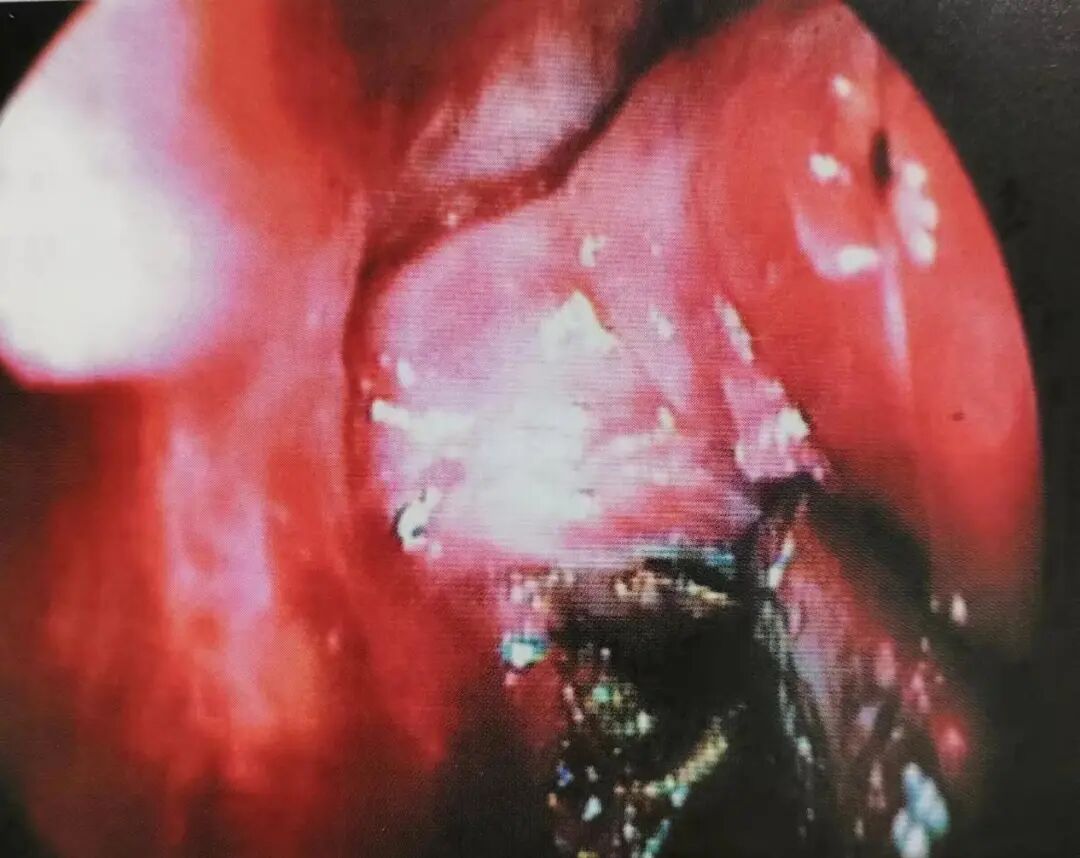

图11小孔由咬骨钳扩大,为了显露蝶腭动脉的主要分支

术中确保咬骨钳顶端位于血管浅表位置极为重要,可防止血管被咬断。去除覆盖在翼腭间隙的骨质范围约1cm,为在其分支点附近夹住蝶腭动脉提供足够空间(图12)。将血管夹放置于邻近的主干及远端分支。暴露的血管以才可吸收止血材料覆盖。若有周围黏膜的持续出血,则以鼻腔止血纱条填塞。鼻硅橡胶薄片放置于鼻中隔两侧,防止术后鼻腔粘连,特别是对于由鼻腔填塞及烧灼造成的广泛性黏膜创伤者。

图12血管夹放置于蝶腭动脉终支附近的主干上